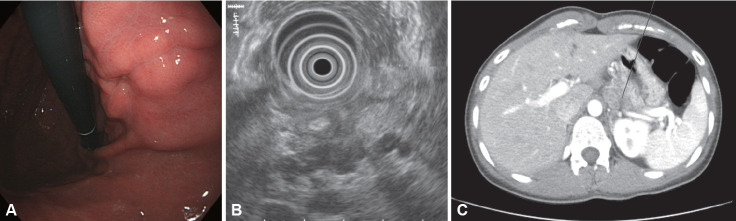

Gastric ulcers are characterized by mucosal damage extending into the submucosa or deeper, with the most common causes being Helicobacter pylori infection and nonsteroidal anti-inflammatory drug use. However, various infectious pathogens, such as pyogenic bacteria, Treponema pallidum, Mycobacterium tuberculosis, viruses, fungi, and parasites, can also cause gastric ulcers. Non-H. pylori infectious gastric ulcers are uncommon and often present with nonspecific symptoms, making their diagnosis challenging. A differential diagnosis requires a comprehensive understanding of the underlying diseases and familiarity with their characteristic endoscopic features. For instance, acute phlegmonous gastritis requires a prompt diagnosis based on typical clinical symptoms and abdominal computed tomography findings, followed by empiric antibiotic therapy. Infections such as gastric syphilis, gastric tuberculosis, cytomegalovirus (CMV) gastritis, and gastric candidiasis necessitate pathogen identification through tissue diagnoses. When this is challenging, the clinical history, endoscopic findings, and serological tests should be integrated to ensure an accurate diagnosis and management. Unlike gastric syphilis and tuberculosis, CMV gastritis and gastric candidiasis often occur secondary to preexisting gastric ulcers; therefore, conventional anti-ulcer therapy is sufficient for immunocompetent patients with mild symptoms. However, antiviral or antifungal agents should be administered to immunocompromised patients and to those with systemic symptoms related to the infection. Similarly, understanding the characteristic history and symptoms of gastric anisakidosis is crucial for an accurate diagnosis, and prompt endoscopic examination is essential to identify and remove the larvae. Clinicians should consider the possibility of infectious gastric ulcers in patients with atypical ulcerative lesions or ulcers that are unresponsive to conventional therapies. Accurate diagnoses and timely treatments are essential for improving patient outcomes.